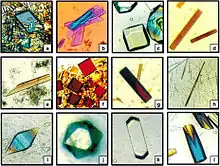

High-quality crystals

While not yet a commercial application, there has been interest in growing crystals in micro-g, as in a space station or automated artificial satellite, in an attempt to reduce crystal lattice defects.[76] Such defect-free crystals may prove useful for certain microelectronic applications and also to produce crystals for subsequent X-ray crystallography.

In 2017, an experiment on the ISS was conducted to crystallize the monoclonal antibody therapeutic Pembrolizumab , where results showed more uniform and homogenous crystal particles compared to ground controls.[77] Such uniform crystal particles can allow for the formulation of more concentrated, low-volume antibody therapies, something which can make them suitable for subcutaneous administration, a less invasive approach compared to the current prevalent method of intravenous administration.[78]

Comparison of insulin crystals growth in outer space (left) and on Earth (right).

Comparison of insulin crystals growth in outer space (left) and on Earth (right).- Liquids may also behave differently than on Earth, as demonstrated in this video